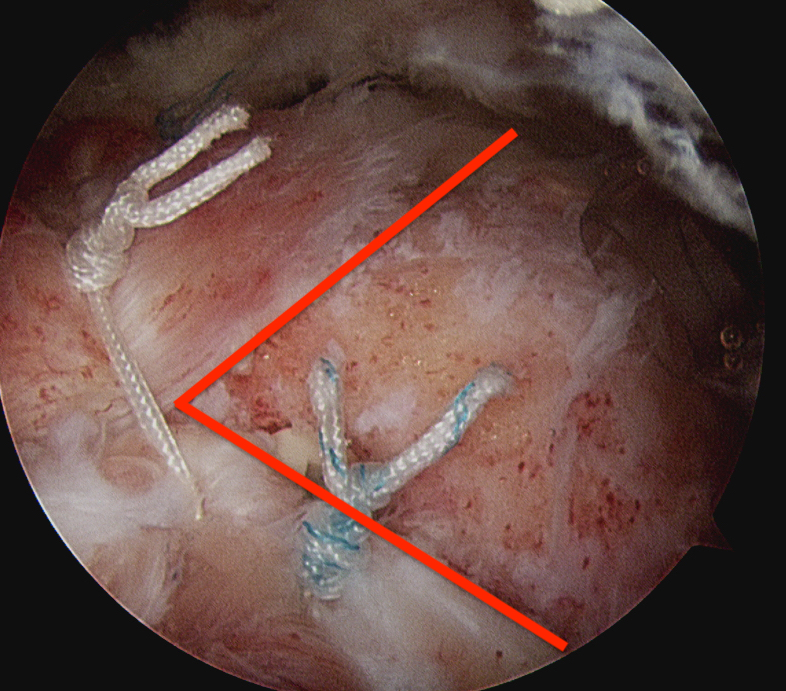

Margin convergence sutures

Release infraspinatus tendon posteriorly and assess mobility

Repair infraspinatus with a combination of margin convergence and posterior suture anchors onto posterior greater tuberosity

True partial repair of the rotator cuff with exposed triangle of greater tuberosity